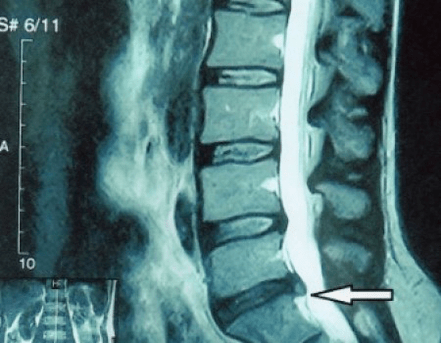

Una “radiografia” del rachide cervicale, e anche con test funzionali di flessione ed estensione, non mostra cartilagine, poiché il suo tessuto trasmette raggi X. Nonostante ciò, in base alla posizione delle vertebre, si possono trarre conclusioni generali sull'altezza dei dischi intervertebrali, sul generale raddrizzamento della curvatura fisiologica del collo - lordosi, nonché sulla presenza di escrescenze marginali sulle vertebre con irritazione prolungata delle loro superfici da parte di dischi intervertebrali fragili e disidratati. I test funzionali possono confermare la diagnosi di instabilità del rachide cervicale.

Poiché i dischi stessi possono essere visti solo mediante TC o MRI, la risonanza magnetica e la tomografia computerizzata a raggi X sono indicate per chiarire la struttura interna della cartilagine e formazioni come protrusioni ed ernie. Pertanto, con l'aiuto di questi metodi, viene effettuata una diagnosi accurata e il risultato della tomografia costituisce un'indicazione, e persino una guida topica, per il trattamento chirurgico dell'ernia nel reparto di neurochirurgia.